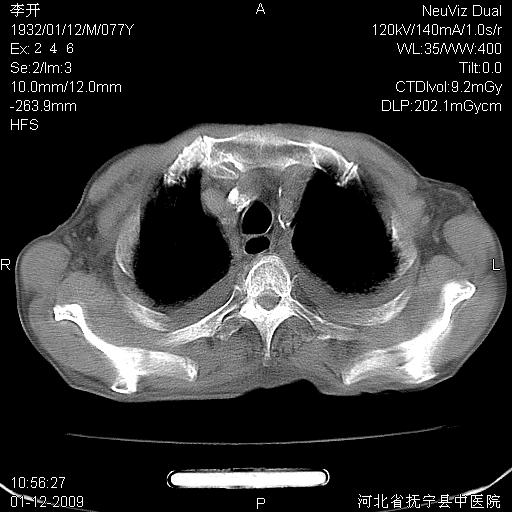

以下是引用黑白光影在2009-1-19 16:49:00的发言:[br]心衰肺水肿;心包、胸腔积液;冠脉钙化;肺部感染。